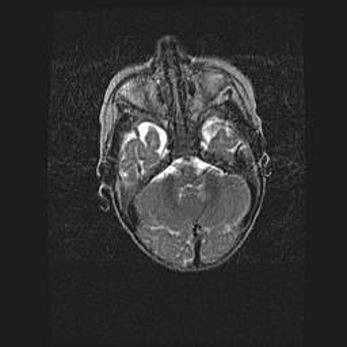

Подострая гематома правой гемисферы мозжечка.

Наружная гидроцефалия.

Возраст: 15 дней

Вес: 3100 г

Пол: женский

Окружность головы: 37 см

Срок гестации: 35-36 недель

При открытой наружной форме гидроцефалии у новорожденных расширяются и переполняются субарахноидные пространства.

Кровоизлияния в мозжечок имеют две клинико-анатомические формы: полушарные гематомы и кровоизлияния в червь.

К появлению этой патологии может привести: повреждения головного мозга, возникающие в результате асфиксии и гипоксии плода при беременности, или травмы во время родов. Редко гематома мозжечка может быть результатом первичной коагулопатии и сосудистой мальформации, диссеминированном внутрисосудистом свертывании, изоиммунной тромбоцитопении.